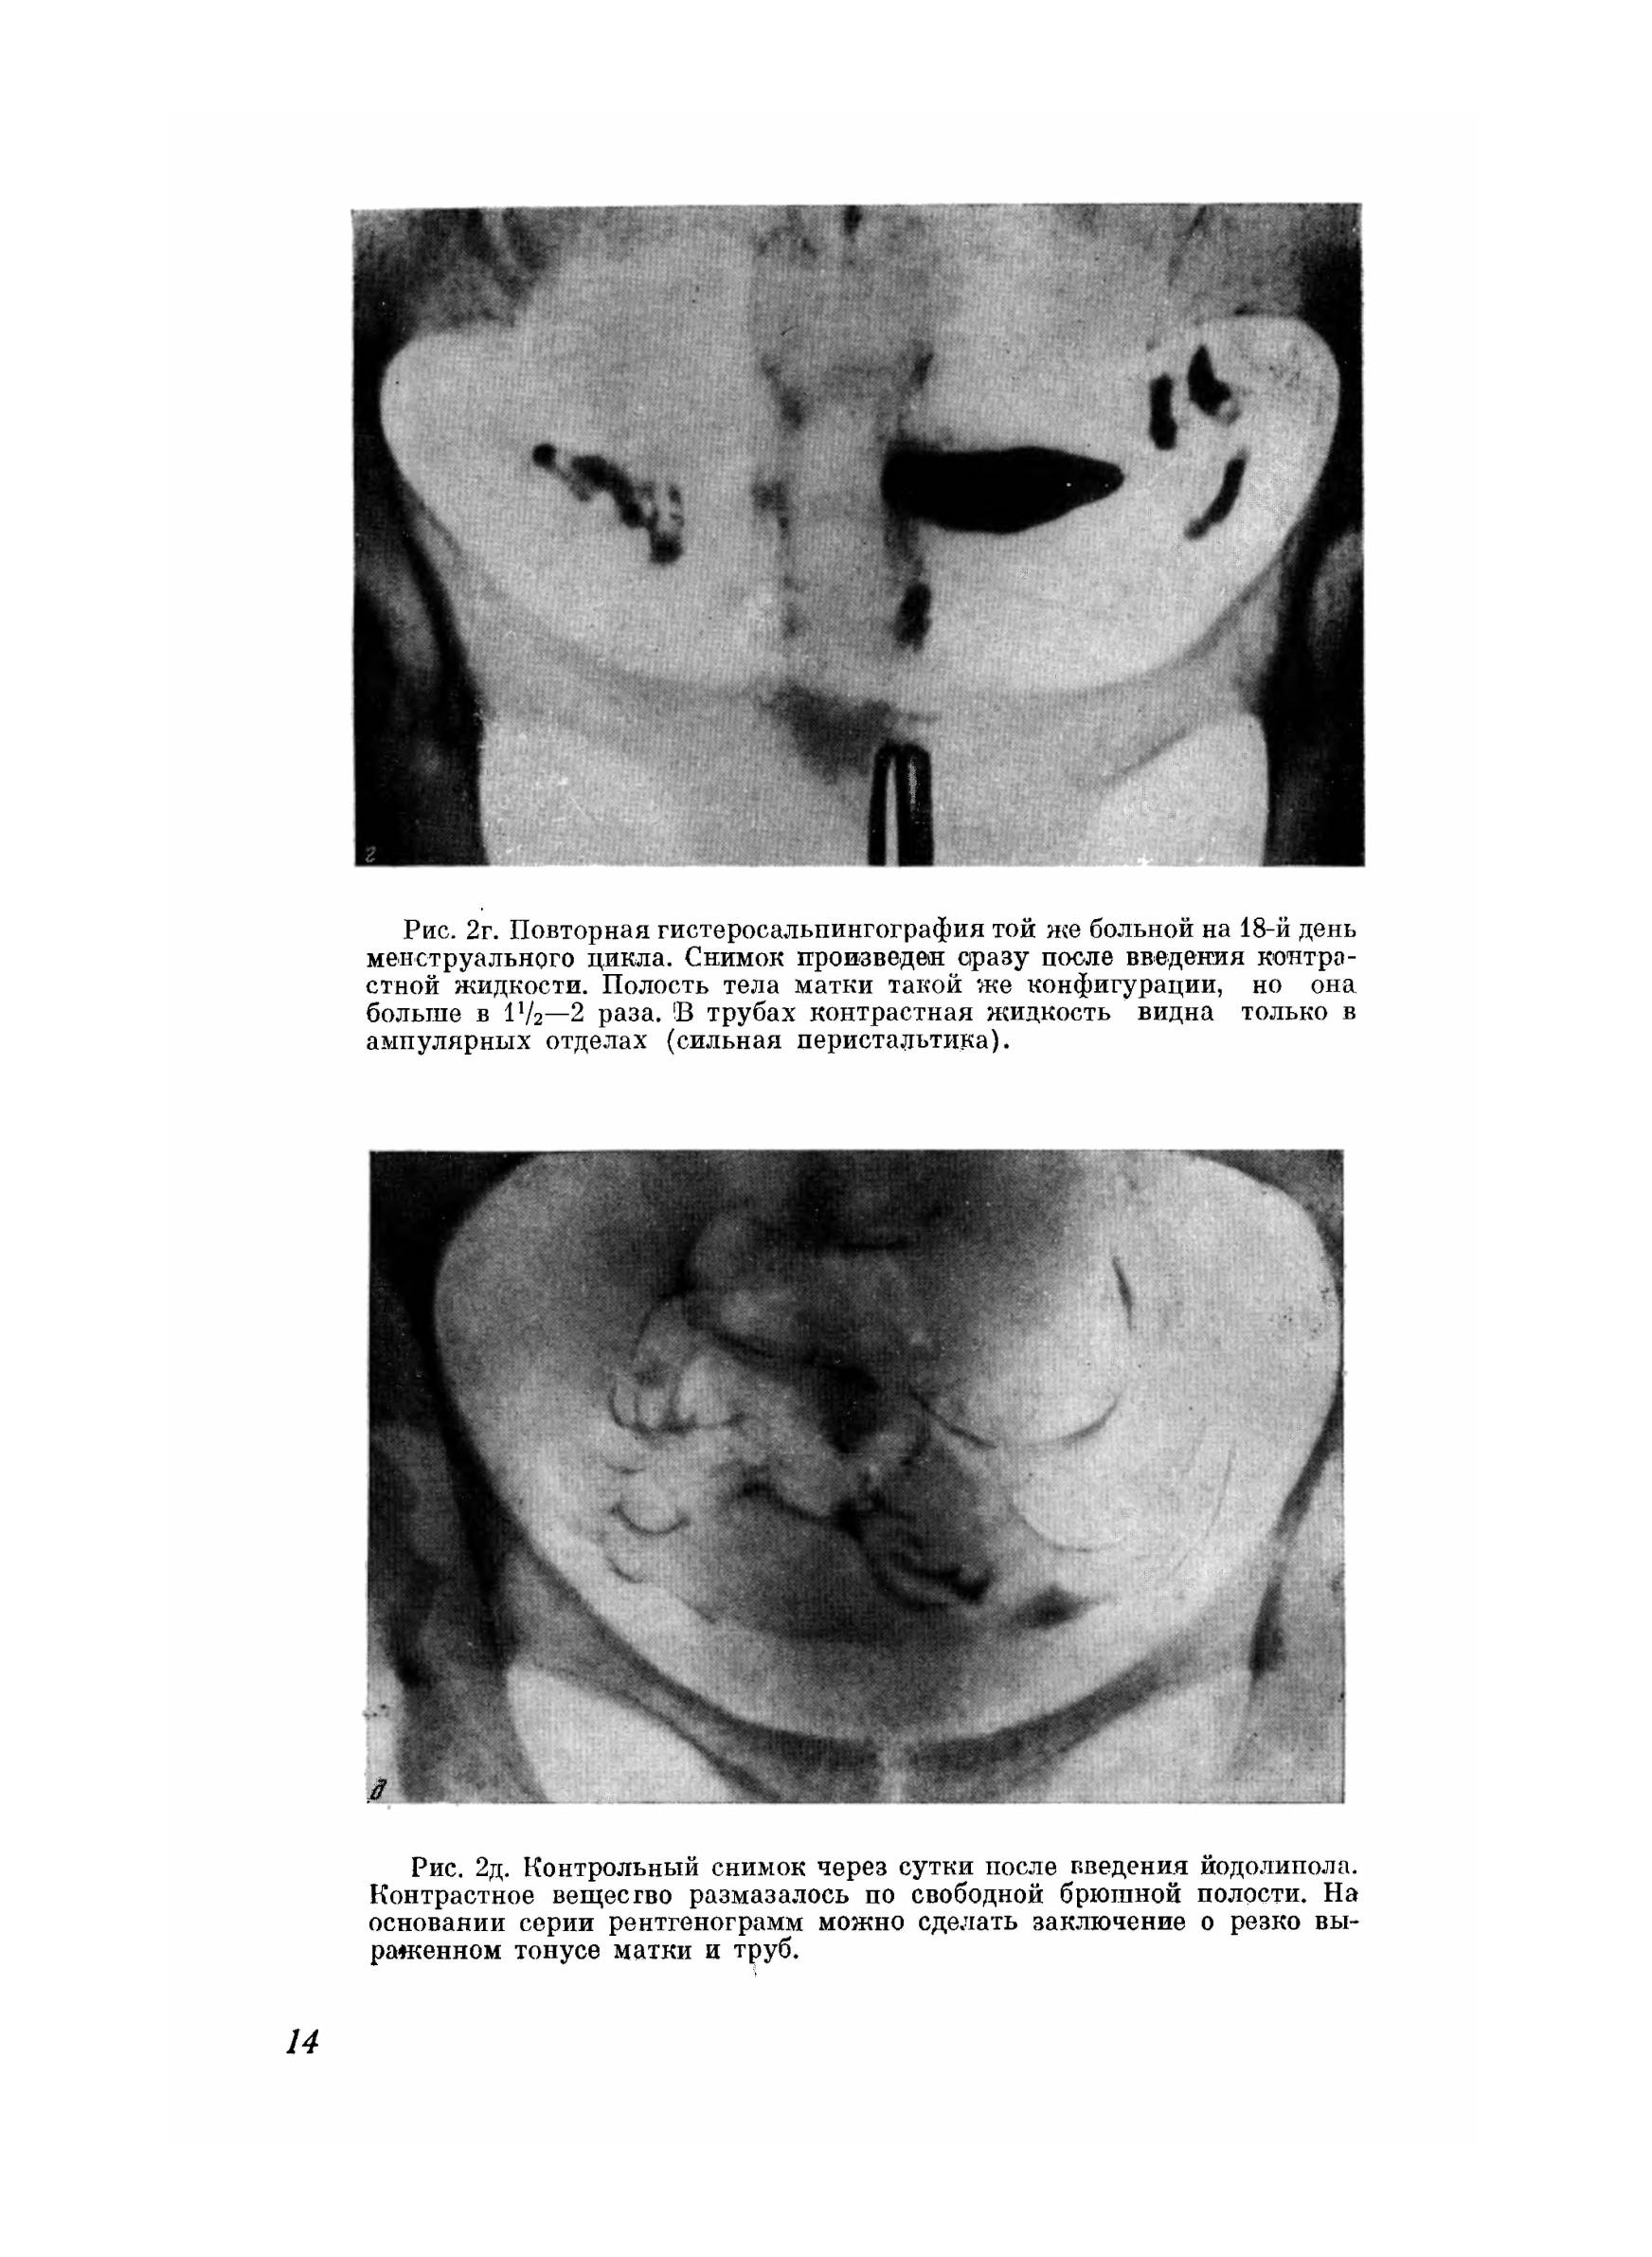

Рентгенологическая диагностика патологических изменений женских подовых органов с помощью контрастной гистеросальпингографии все шире и шире находит практическое применение, она помогает поставить правильный диагноз и применить целесообразный метод лечения. Многие врачи-гинекологи вследствие неумения читать рентгенограммы предоставляют их на интерпретацию рентгенологам общего профиля, которые дают заключение без достаточных знаний гинекологии, не учитывая особенности условий и техники проведения гистеросальпингографии. Гистеросальпингографии является объективным и документальным методом в оценке проходимости или непроходимости труб. В этом заключается одно из преимуществ его перед продуванием последних. Гистеросальпингография дает четкие контуры слизистой матки и труб и дефекты наполнения их полостей, на основании которых можно установить тот или иной диагноз (туберкулезный эндометрит, эндометриоз, полипы, миомы и т. д.). Желание помочь практическому врачу в проведении гистеросальпингографии и дать возможность разобраться в многообразных рентгенологических картинах привело нас к мысли поделиться своим опытом и выпустить альбом, в котором помещено около 150 рентгенограмм, размещенных по разделам соответственно тематики. Считаем, что подготовка кадров акушеров-гинекологов, владеющих не только правильной техникой гистеросальпингографии, но и умением хорошо разбираться в каждой рентгенограмме, обеспечит наиболее правильную диагностику и своевременное применение рациональной терапии.